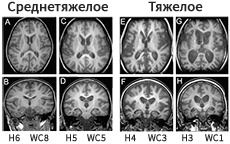

МРТ головного мозга

В начале заболевания показатели МРТ головного мозга могут быть в пределах нормы или имеют незначительные отклонения. К отклонениям, которые позволяют заподозрить НЦЛ2, относятся1,2:

• атрофия головного мозга ‒ распространенная патология у больных НЦЛ;

• гиперинтенсивность сигнала белого вещества в перивентрикулярных зонах головного мозга.

На более поздних этапах заболевания атрофия головного мозга становится очевидной и продолжает прогрессировать1,2.

Worgall S et al. Neurology. 07.08.2007, 69 (6): 521-35.